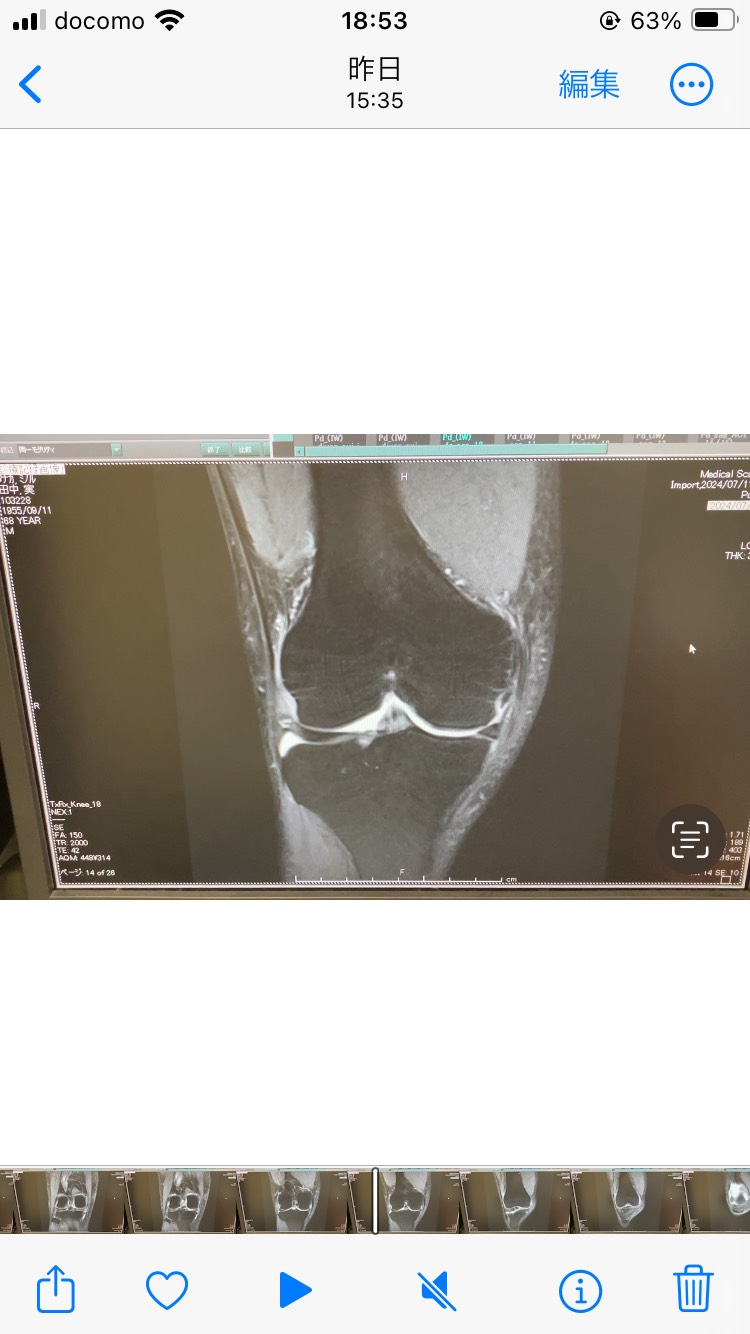

IMG_0755

2025.01.31 | Category: